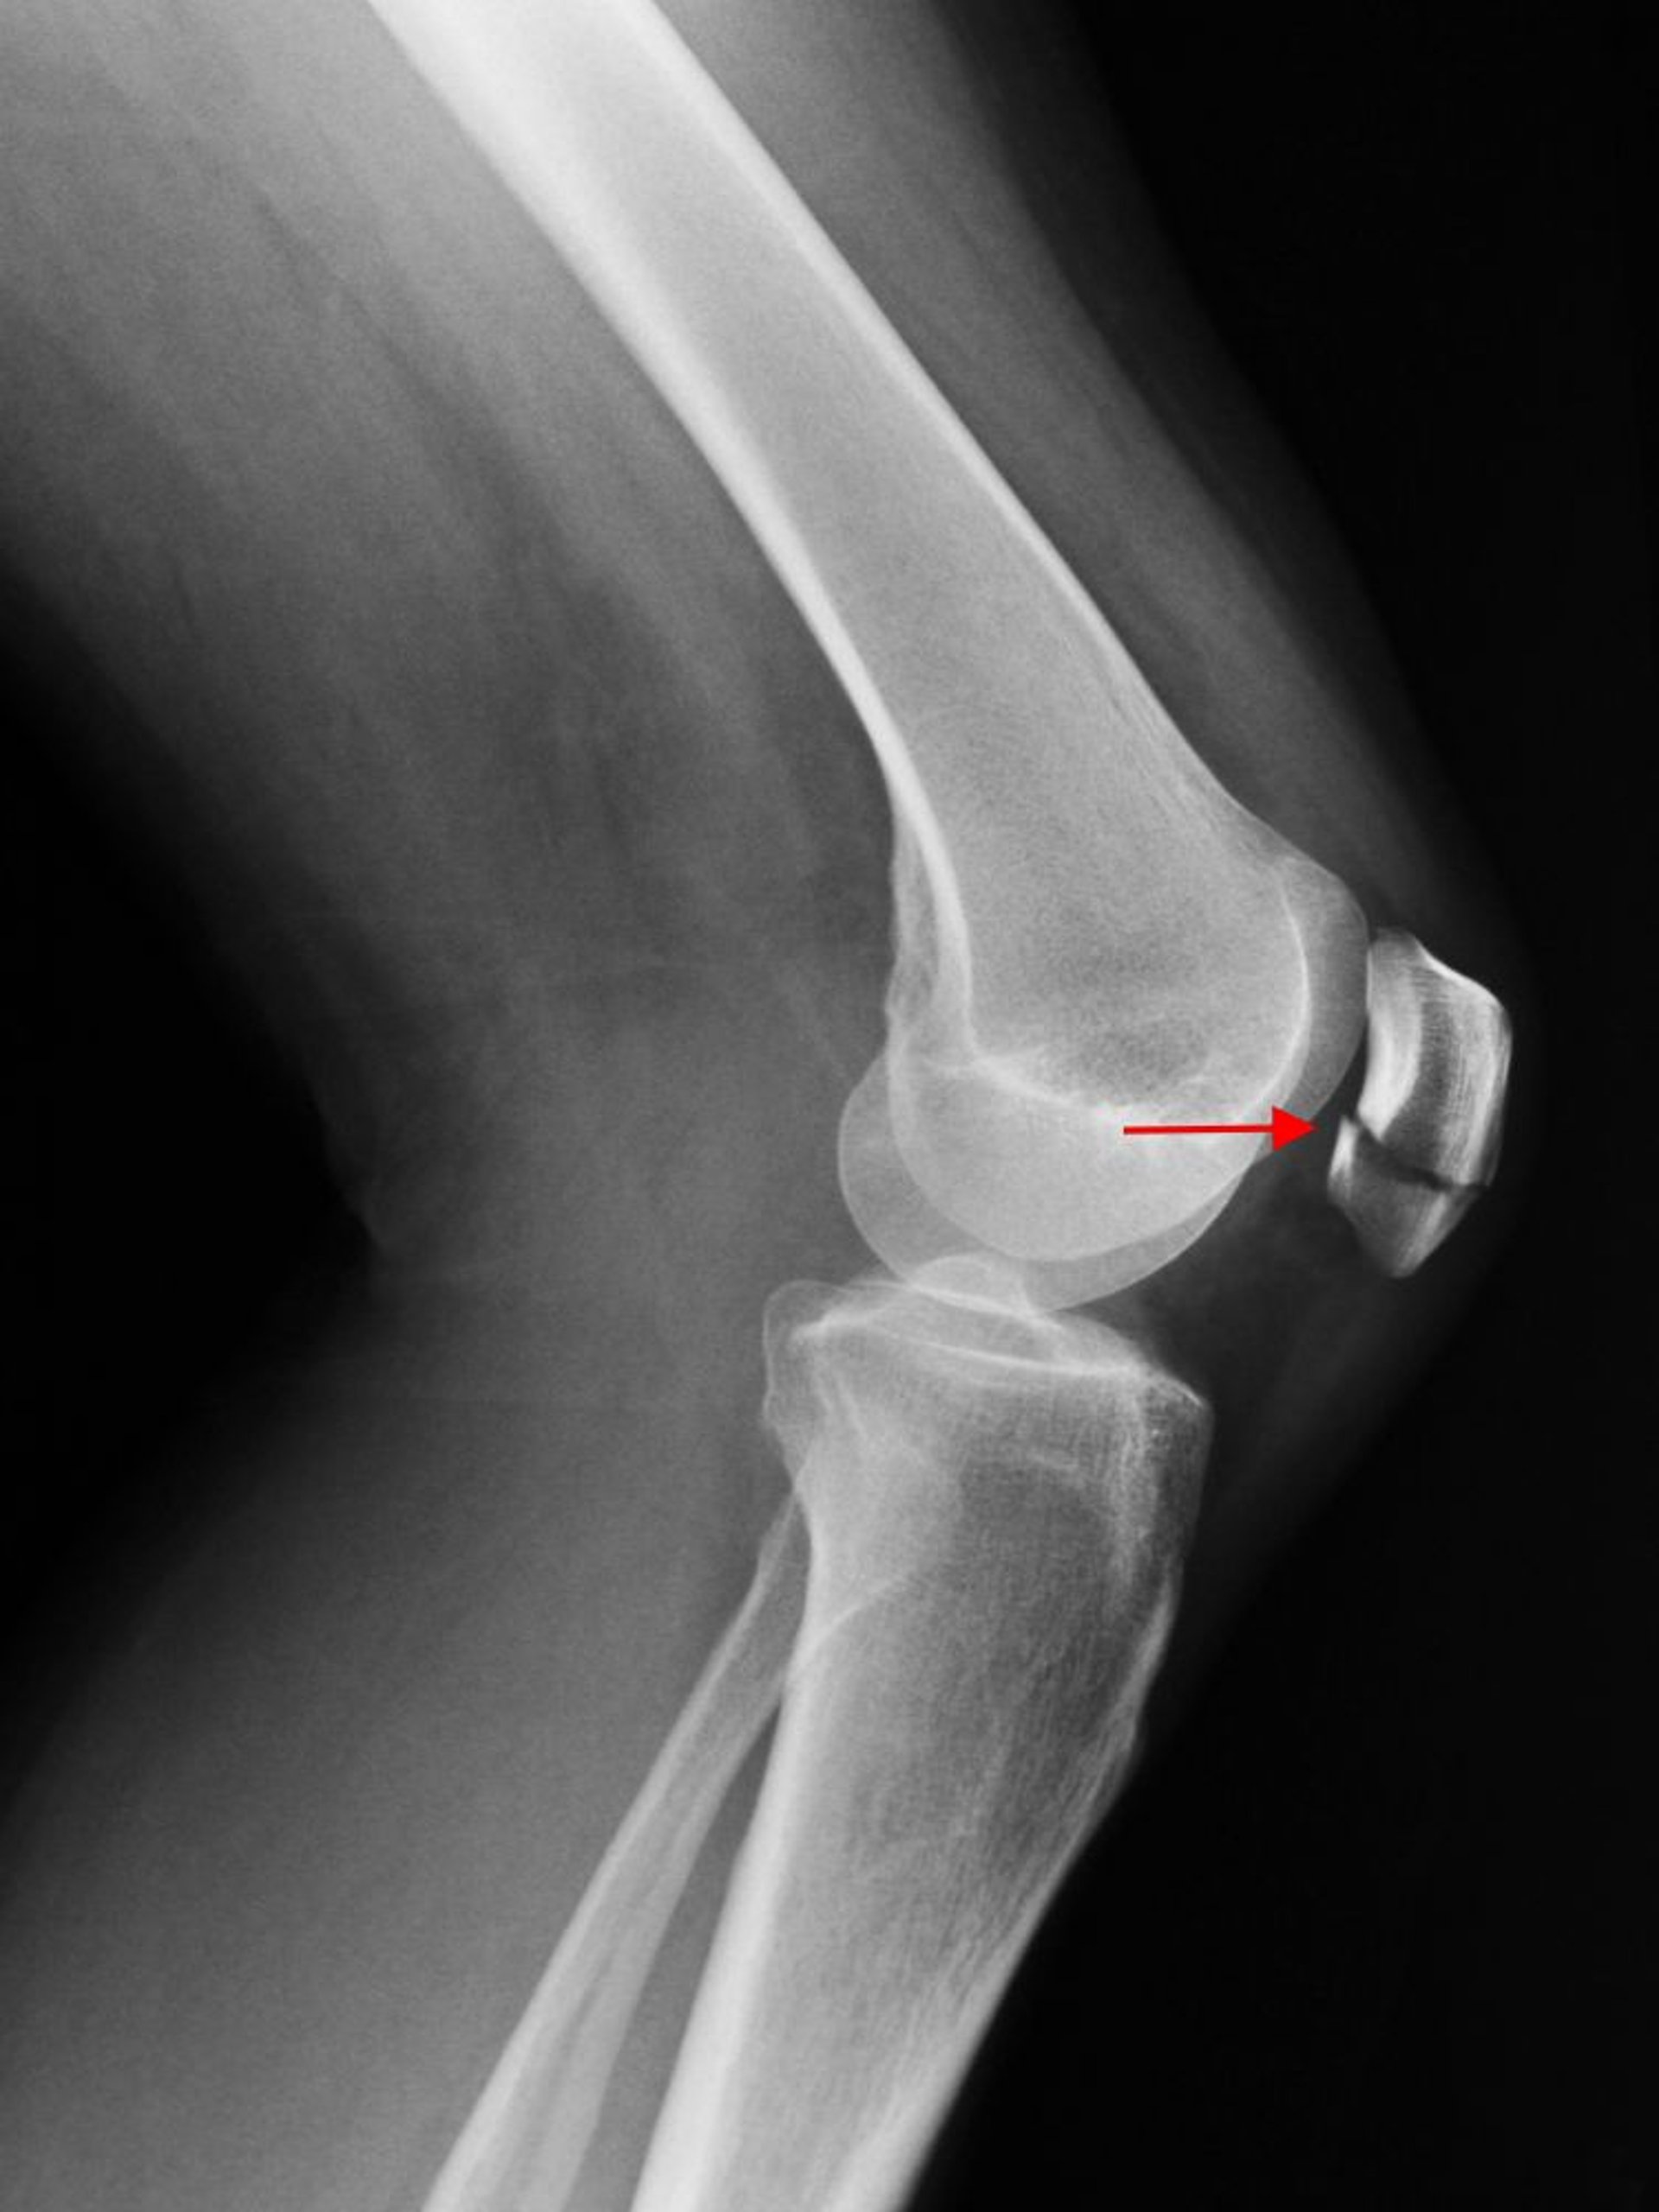

Gãy xương bánh chè

X-quang khớp gối nghiêng cho thấy một đường gãy ngang của xương bánh chè (mũi tên).